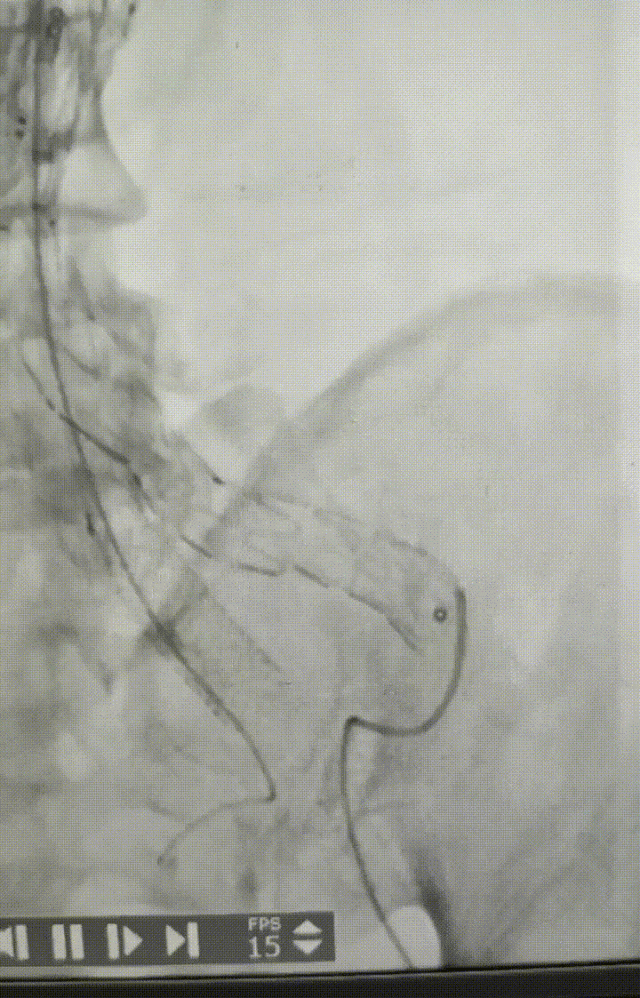

术后情况:造影提示动脉瘤完全隔绝,手术成功实现了保留双侧髂内动脉并隔绝动脉瘤的目标,患者病情得到有效控制。

术后造影